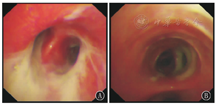

急性期住院期间,26例均因肺实变、广泛渗出而接受支气管镜检查,镜下多表现为黏膜充血、糜烂,2例并发塑型性支气管炎(图2)。15例合并PIBO的支气管扩张症患儿随访过程中因急性加重行支气管镜检查。镜下表现均为黏膜充血,管腔大量淡黄色黏稠分泌物,仅1例见"鱼骨征"(图3)。